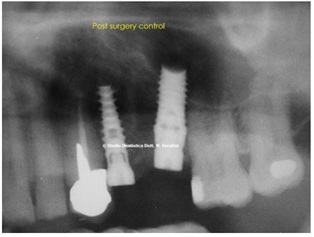

Within six to eight months, we will achieve a reduction in the air volume of the maxillary sinus with the formation of new regenerated bone starting from the old border & / or floor of the maxillary sinus, with implants allocated and osseointegrated (Figures 10-12).

Figure 10: X-ray post Surgery control.